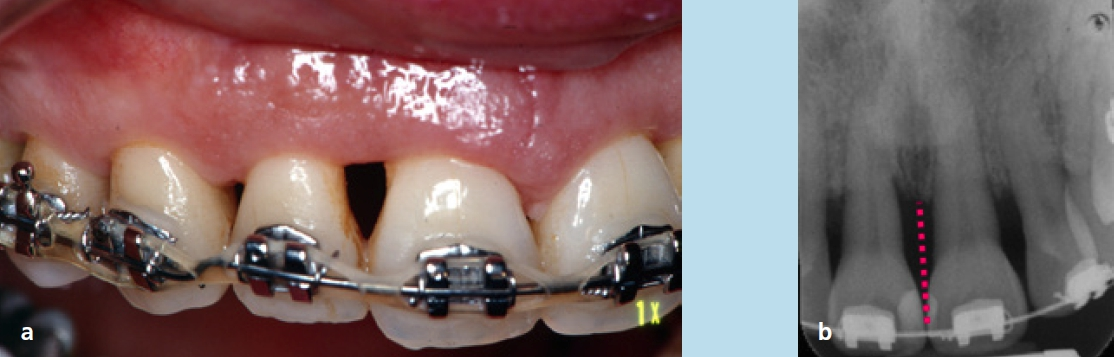

Für die Behandlung und geplanten Zahnbewegungen wurde eine festsitzende Apparatur (0,022 × 0,028 Slot-Brackets) eingegliedert; im Oberkiefer erfolgte eine vollständige Bebänderung, im Unterkiefer nur eine Teilbebänderung der Seitenzähne (Abb. 22a bis c). Aufgrund der Achsenstellung der Fronten im Unterkiefer sollte eine weitere labiale Kippung bei der Auflösung des Engstandes vermieden werden. Um dies weitestgehend umsetzen zu können, wurde im gesamten Frontzahngebiet und bei den seitlichen Zähnen inklusive der Mesialfläche der Unterkiefereckzähne um insgesamt 4 mm gestrippt (0,20 bis 0,25 je Approximalfläche). Die Form der Zähne und der Verlauf der Gingiva ließen dies zu. Zu Beginn der Behandlung wurden nur die 1. Molaren, Prämolaren und Eckzähne bebändert, um die Proklination der unteren Schneidezähne zu vermeiden. Die Prämolaren wurden jeweils von mesial und distal sowie die Eckzähne von distal mit dem oszillierenden EVA-Winkelstück mit Hubbewegung gestrippt. Für eine effektive Distalisation und Ausnutzung des gewonnenen Platzes wurde in den Bogen zwischen den Zähnen 33 und 43 eine Druckfeder eingesetzt (Abb. 23). Nach vollständiger Distalisation der seitlichen Zähne wurden die Schneidezähne beklebt. Vor dem Einligieren des Bogens wurde die Unterkieferfront von mesial und distal einschließlich der mesialen Fläche der Eckzähne gestrippt. Es wurden Lace-backs und voller Bogen eingesetzt (Abb. 24a bis c).

Ziel einer kieferorthopädischen Behandlung ist die Rehabilitation der Funktion und Ästhetik, die aber auch stabil gehalten werden soll. Die Aneinanderreihung der Zähne sichert die Kontinuität des Zahnbogens und unterstützt dessen Stabilität; fehlt ein Kontaktpunkt, weil ein Zahn fehlt, ist das Gleichgewicht zerstört und die Zähne, die an die Lücke angrenzen, verschieben sich gegeneinander. Wheeler [37] unterstreicht den funktionellen Aspekt des Approximalkontaktes, indem er ihn als „semimobiles Gelenk“ bezeichnet, das es ermöglicht, die Kraft, die auf einen der Zähne einwirkt, auf eine wesentlich größere Anzahl von Zähnen zu verteilen. Aus diesem Grund ist manchmal die Schmelzreduktion erforderlich, um bessere und stabile Zahnkontakte zu bekommen [38]. Was den interradikulären Knochen betrifft, kann eine Verkleinerung des Zahnzwischenraums zu einer Annäherung der Wurzeln führen. Wird der interradikuläre Spalt unter 0,5 mm verringert, verschwindet der medulläre Knochen. Bei einer Annäherung unter 0,3 mm verschwindet außerdem die Lamina dura und es kommt zu einer Verbindung der Zähne über die parodontalen Ligamente. Die Folge sind laterale Wurzelresorptionen [14]. Aus diesem Grund sollten die Wurzelabstände vor dem Strippen bewertet werden. Giovanoli bemerkt jedoch, dass eine Wurzelresorption nicht ohne pathologischen parodontalen Prozess eintreten kann und dass dieser Situation in aller Regel eine laterale Wurzelresorption der proximalen Fläche der betreffenden Zähne vorausgeht [14]. Eine minimale interradikuläre Distanz liegt vor, wenn der Zahnkontakt deutlich zervikal liegt. In diesem Fall ist das Strippen absolut kontraindiziert, selbst wenn der Zahn breiter als der Durchschnitt ist. Die Reduzierung des medullären Knochens führt zu einer verbesserten parodontalen Abwehrkraft, andererseits reduziert sich aufgrund der starken Vaskularisierung die Regenerationsfähigkeit. Bei Patienten mit parodontalen Erkrankungen ist daher Vorsicht geboten.